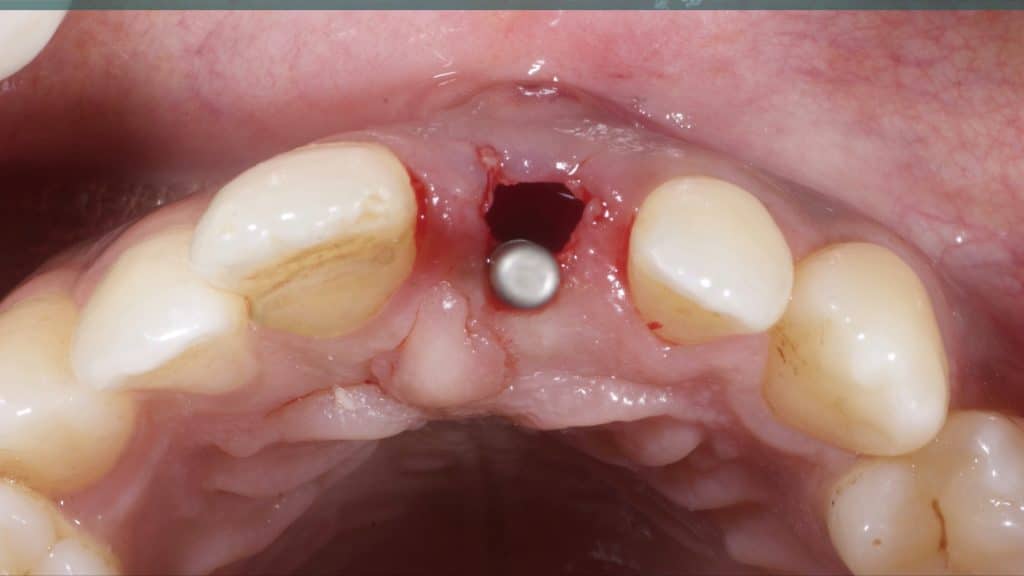

A 27-year female patient with dislodged Resin bonded FPD. She had that FPD for past few years, it had metal wings on palatal surfaces of UR1 and UL2 and a post like metal extension into the root canal of UL1. There was gingival abscess due to fractured root segment most probably due to extended metallic post like structure. Immediate implant placement (IIP) and Immediate restoration (IR) was planned for this patient.

Immediate post-op